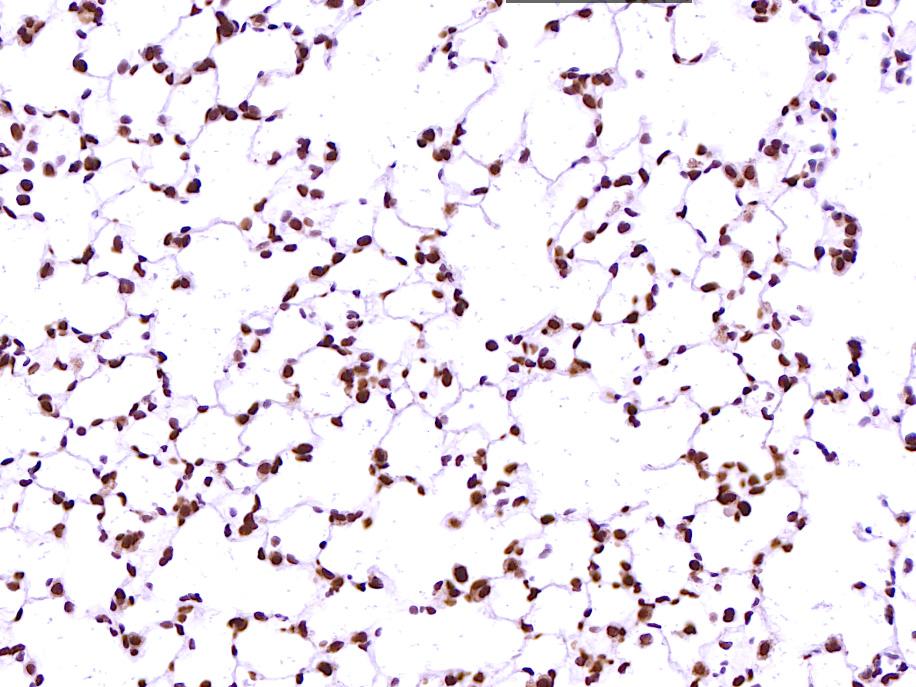

tunel染色(白光)含扫片

编号:YSY10112

tunel染色(荧光)含扫片

编号:YSY10113

tunel分析

编号:YSY10114